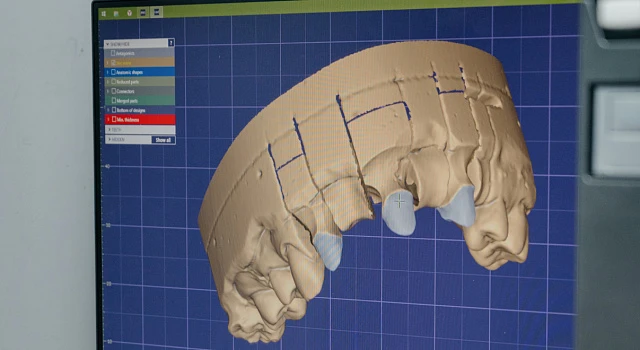

Цифровая диагностика и визуализация

Цифровая диагностика и визуализация

Полное обследование полости рта

Снятие оттиска

Определение прикуса

Визуализация цифровой модели челюсти

Индивидуальный подход и планирование — основа безошибочной имплантации

Мы не устанавливаем импланты «на глаз»

Перед имплантацией «Все на 4» в клинике «Один к Одному» проводится расширенная 3D-диагностика по 65 параметрам

3D — моделирование будущей улыбки

3D — моделирование будущей улыбки

Создание виртуальной модели будущей улыбки с учетом показателей диагностики, которое позволяет пациенту увидеть и даже «примерить» новые зубы еще до начала лечения

Планирование положения имплантов

Планирование положения имплантов

Моделирование расположения имплантов для их оптимального положения относительно соседних зубов, нервов и мягких тканей

Создание хирургического шаблона и протокола имплантации

Создание хирургического шаблона и протокола имплантации

Планирование глубины, диаметра и оси введения импланта для гарантии высочайшей точности операции. Установка имплантов в единственно правильной позиции с помощью хирургического шаблона